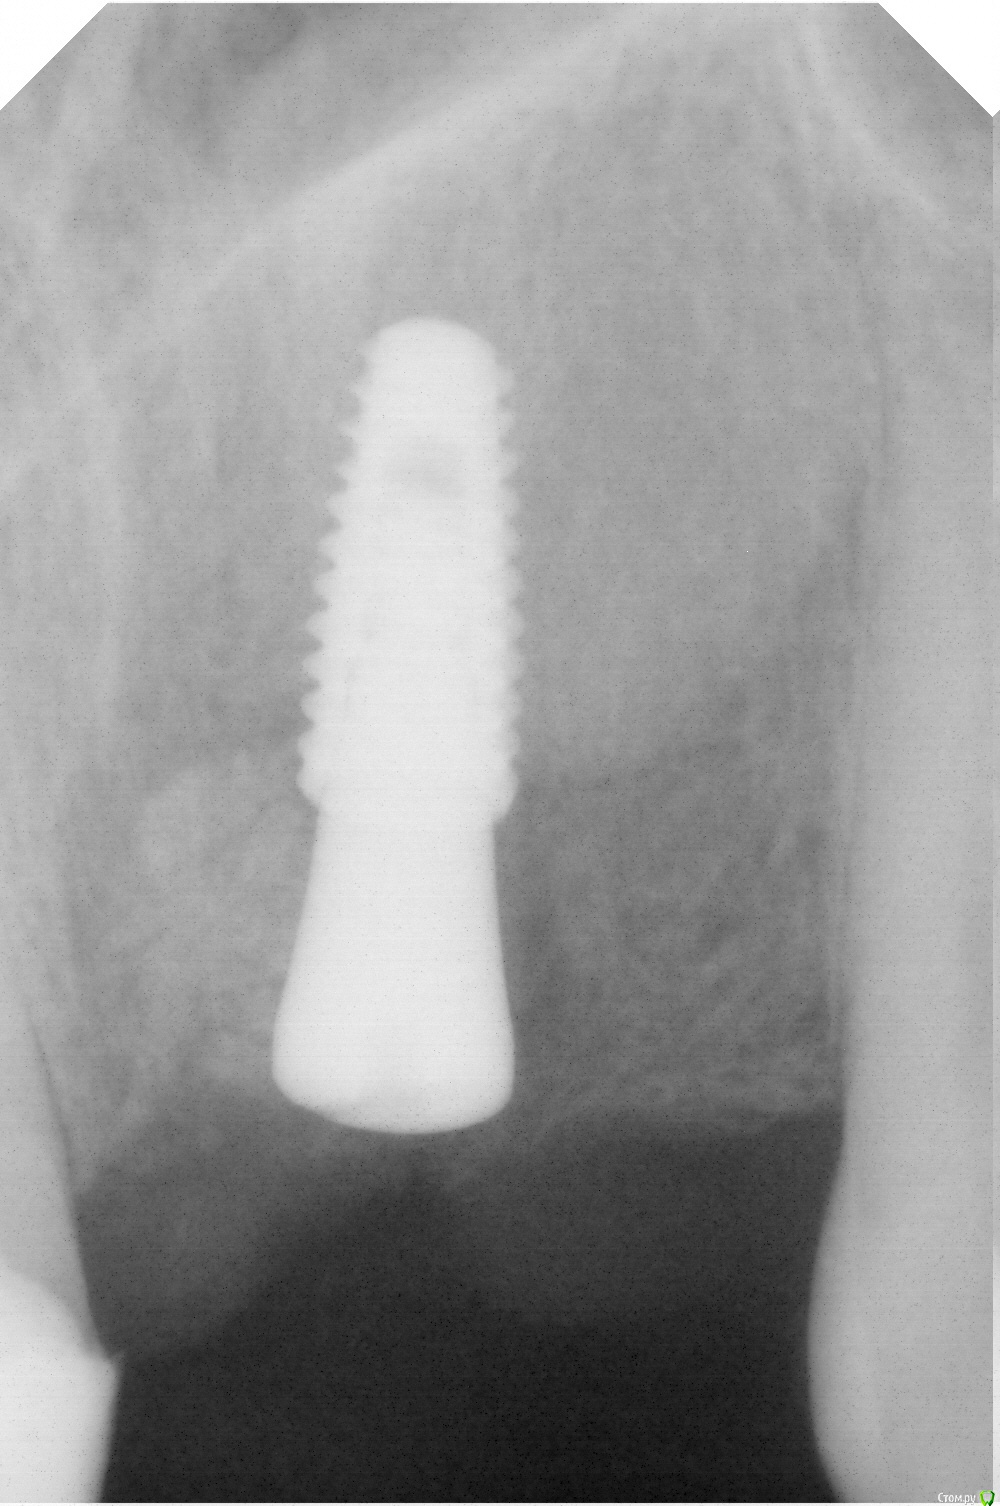

bogdan_r Опубликовано 28 февраля, 2019 Автор Поделиться Опубликовано 28 февраля, 2019 (изменено) Доброго дня. Спасибо всем за советы. Удалил зуб. Почистил грануляции, установил имплантант 4.0*10 Anyone Megagen. Хотел сразу установить формик, а кость была не очень плотная, поэтому заглубил имплантант на 6 мм от уровня десны и 4 мм от небной стенки. Знаю, что глубоко. Может чуть-чуть открутить имплант? Прошло 5 дней. Торк был 25Н Изменено 28 февраля, 2019 пользователем bogdan_r Ссылка на комментарий

bogdan_r Опубликовано 28 февраля, 2019 Автор Поделиться Опубликовано 28 февраля, 2019 Вот фото Ссылка на комментарий

bogdan_r Опубликовано 28 февраля, 2019 Автор Поделиться Опубликовано 28 февраля, 2019 Ещё одно фото Ссылка на комментарий

bogdan_r Опубликовано 28 февраля, 2019 Автор Поделиться Опубликовано 28 февраля, 2019 Тут лучше видно Ссылка на комментарий

Борис80 Опубликовано 28 февраля, 2019 Поделиться Опубликовано 28 февраля, 2019 ну считается, что десна не способна жить, если её высота больше 5 мм от уровня костной ткани... 4-5 мм оптимальное заглубление Ссылка на комментарий

___49___ Опубликовано 1 марта, 2019 Поделиться Опубликовано 1 марта, 2019 (изменено) А что скажите про глубину? кажется глубоко . Может чуть-чуть открутить имплантантконус о приоре чуть- чуть открутить невозможно - он просто вывалится - только если перекрутиться другим имплантом . а в вашем случае единственный вариант чтоб обойтись меньшей кровью - это более узкий ФДМ,но такой подход не очень хорош уже в конкретном случае.... Я вообще к фронтальным имплантам подошел только после учебы по НКР - для меня это пока еще сложнее чем синус или расщепление. Изменено 1 марта, 2019 пользователем ___49___ Ссылка на комментарий